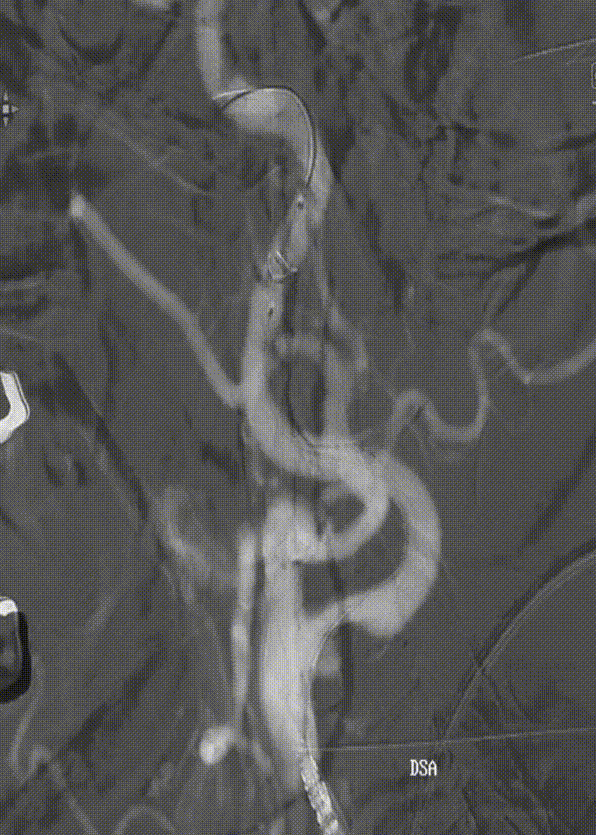

使用雅培Workhorse保护伞导丝先行通过病变狭窄处,随后将Emboshield Nav6保护伞沿导丝推送经过C1端弯曲处。借助Nav6保护伞的支撑,推送6F 115cm中间导管至C1远端,利用特洛伊木马技术将Nav6保护伞输送并放置于颈内动脉C1段。回撤中间导管,在透视状态下释放Nav6保护伞,Nav6圆周骨架在透视下显影清晰,定位准确。